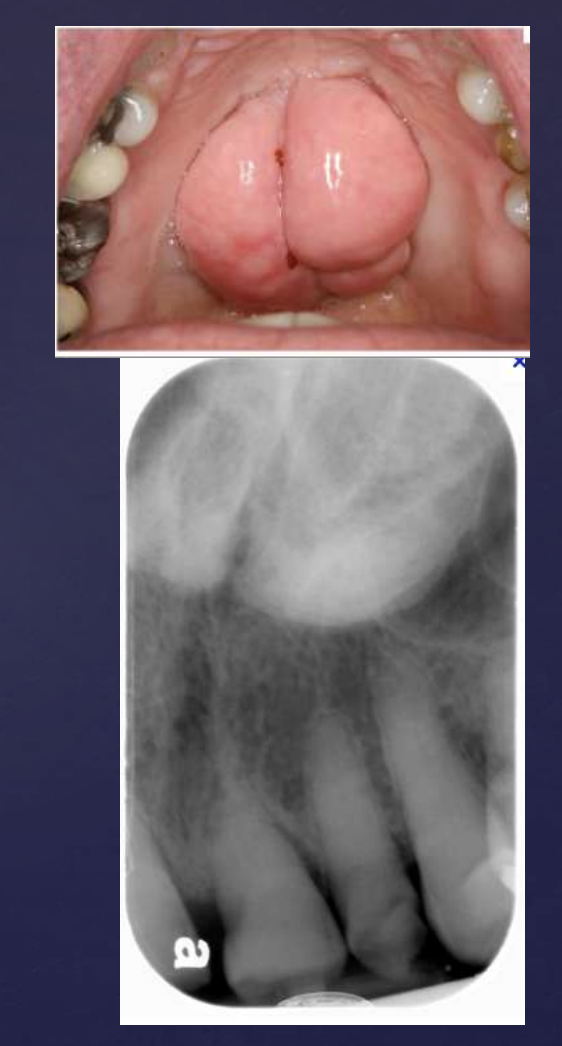

Unicystic Ameloblastomas

expansion/thinng ext. oblique ridge

Adenomatoid Odontogenic Tumor

Well defined, corticated

Mixed density (predominantly radiolucent with some radiopacity within)

Associated with impacted maxillary lateral incisor

Displacement of adjacent teeth